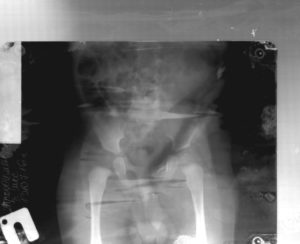

УЗИ тазобедренных суставов было проведено 395 детям в возрасте до 6 мес по методу Г. Рейнгарда [3] с одновременной оценкой развития костно-хрящевого соотношения сустава, определением сонографических типов тазобедренных суставов.

В ходе обследования тазобедренных суставов у 395 детей были выявлены следующие типы тазобедренных суставов.

По результатам УЗИ у 286 (72,41%) детей диагностированы типы 1а и 1б тазобедренных суставов (по Г. Рейнгарду). Клинически и сонографически типы 1а и 1б соответствуют возрасту ребенка – это здоровые суставы.

Костная часть вертлужной впадины хорошо определяется, костный эркер слегка сглажен или прямоугольный, хрящевая часть крыши охватывает головку бедренной кости, костно-хрящевое соотношение больше или равно 2/3. Угол α больше или равен 60°.

Тип 2а тазобедренных суставов (рис. 3) диагностирован у 46 (11,6%) детей. Это вариант физиологической задержки развития тазобедренных суставов у детей в возрасте до 12 нед, при котором угол α меньше 59°, но больше 50°, соответственно угол β больше 60°.

Тип 2б тазобедренных суставов выявлен у 25 (6,33%) детей – дисплазия тазобедренных суставов у детей старше 3 мес (рис. 4). Костная вертлужная впадина недостаточно развита, костный эркер закруглен, костнохрящевое соотношение меньше 2/3, хрящевая часть крыши охватывает головку бедренной кости. Угол α меньше 59°, но больше 50°, угол β больше 60°.

Тип 2с тазобедренных суставов (рис. 5) обнаружен у 2 (0,51%) детей. Это вариант тяжелой дисплазии в любом возрасте. Все составляющие сустава недоразвиты.

Костная часть вертлужной впадины уплощена, костный эркер закруглен или плоский, хрящевая часть вертлужной впадины расширена, но еще охватывает головку бедра. Угол α меньше 49°, но больше 43°, угол β больше 65°, но меньше 72°.

Такой тип суставов без соответствующего лечения, влечет прогрессирующее децентрирование головки бедра.

У 1 (0,25%) ребенка выявлен 3а тип тазобедренного сустава – врожденный вывих бедра (рис. 6). Костная часть вертлужной впадины и эркер плоские, хрящевая часть вертлужной впадины смещается краниально, так как головка бедра не может быть зафиксирована в вертлужной впадине, происходит ее децентрация. Структура хрящевой части крыши не изменена. Угол α меньше 43°.

Все 106 детей, с выявленной патологией, были направлены на консультацию к врачу-ортопеду. После курса физиотерапии, широкого пеленания, при необходимости, на контрольном УЗИ (50 детей), были выявлены следующие изменения:

Из 8 детей с простой двусторонней дисплазией тазобедренных суставов, без пространственных нарушений, с задержкой сроков оссификации, у 2 изменений не наблюдалось, а у 6 детей сроки оссификации соответствовали возрасту.Из 25 детей с тазобедренными суставами типа 2а после проведенного курса лечения у 10 установлен тип 1а, у 7 – тип 1б, у 3 – тип 2б, у 5 детей имела место простая двусторонняя дисплазия тазобедренных суставов, без пространственных нарушений, с задержкой сроков оссификации.Из 17 детей с тазобедренными суставами типа 2б после проведенного курсалечения у 5 установлен тип 1а, у 7 – тип 1б, у 1 – тип 2б, у 4 детей сохранялась простая двусторонняя дисплазия тазобедренных суставов, без пространственных нарушений, с задержкой сроков оссификации.

В результате 35 (70%) детей со своевременно диагностированной патологией после проведенной терапии имеют здоровые суставы 1-го типа, 15 (30%) детей, с сохранившейся патологией были направлены на повторный курс терапии.